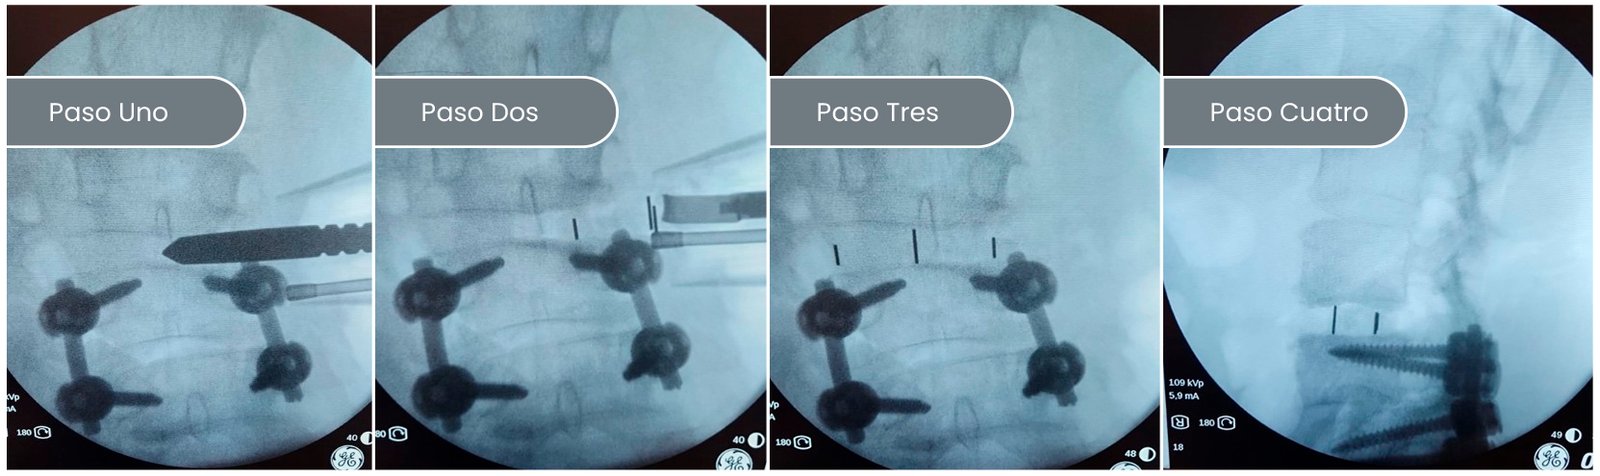

El XLIF o abordaje lateral para un caso de combinación de abordajes de escoliosis del adulto:

Primero el preoperatorio y luego los pasos intra. en este caso, la paciente estaba operada hacia 5 años y se lateralizó y quedó torcida. entonces le planifique la corrección en un día quirúrgico. bajo la misma anestesia le realizamos el abordaje lateral donde van las cajas. a continuación, la acuesto boca abajo y le colocamos todos los tornillos y barras para terminar la corrección. Esta paciente lleva operada 7 meses.

PASOS DEL XLIF CON LA PACIENTE EN DECÚBITO LATERAL

SEGUNDA CAJA

SEGUNDA CAJA LATERAL COLOCADA

CHEQUEADO TODO EN ORDEN, SE POSICIONA BOCA ABAJO Y COMENZAMOS EL SEGUNDO ABORDAJE A LA COLUMNA PARA CORRECCIÓN Y ESTABILIZACIÓN DEFINITIVA